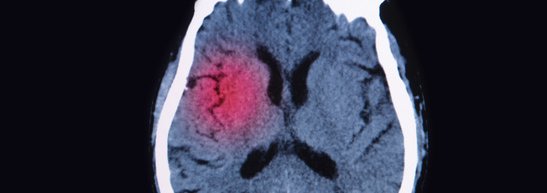

Magnetic resonance imaging (mri) is a medical imaging technique used in radiology to form pictures of the anatomy and the physiological processes of the body. Using magnetic resonance imaging, a doctor can create pictures of tissues, organs, and other bodily components and view them on a computer. Image courtesy of ucla health. The mri scan did reveal a few small lesions consistent with smith's history of brain trauma. Someday soon, doctors may use a slightly tweaked but common brain imaging test to detect a neurodegenerative disorder that especially affects athletes — if recent research published in the american journal of geriatric psychiatry continues to hold up.

Both Pcs And Cte Are Considered Neurological Disorders Which Are Long Term Effects Of A Concussion While Both Brain Diseases Post Concussion Syndrome Ct Scan from i.pinimg.com Checking images page the body radiologist to check images if you have any questions regarding the exam. Pituitary adenoma, craniopharyngioma, and rathke cleft cyst involving both intrasellar and suprasellar regions: While the findings from this single case report are preliminary, they raise the possibility that mri scans could be used to diagnose cte and related conditions in living people. Healthy brain mri scan post concussion brain mri human brain mri cte mnd concussion brain mri white matter cte brain comparison. Magnetic resonance imaging (mri) is a medical imaging technique used in radiology to form pictures of the anatomy and the physiological processes of the body. Bleeding edge medical technology as of 2019. Beersheba, israel) have revealed that brain imaging techniques could be used to determine. The mri scan did reveal a few small lesions consistent with smith's history of brain trauma.

Magnetic resonance imaging (mri) uses magnetic fields and radio waves to produce detailed images of the inside of your body. Researchers report mri brain scans may be an early and easier way to diagnose cte. The cni has stored example protocols for anatomical, fmri, diffusion, spectroscopy and quantitative mr scans (named as cni examples, stored under cni / head). The various mri patterns of pituitary apoplexy. > transient ischaemic attack (tia), cerebrovascular attack (cva) > infection, inflammation, meningitis, encephalitis, hiv, aids, tb. Cte has been known to affect boxers since the 1920's (when it was initially termed punch drunk syndrome or dementia pugilistica). It is often used for disease detection, diagnosis, and treatment monitoring. The mri scan did reveal a few small lesions consistent with smith's history of brain trauma. Using magnetic resonance imaging, a doctor can create pictures of tissues, organs, and other bodily components and view them on a computer. Questions and answers in mri. This section of the website will explain planning for various types of mri scans, mri protocols, positioning for mri, and common indications indications for mri brain. In this video lecture, we review the appearance of the liver on multiphase ct & mri. How do mri and mrcp compare to other imaging tests?

Science Source Stock Photos Video Chronic Post Traumatic Brain Injury Mri from www.sciencesource.com This article presents a simplified approach to recognizing common mri sequences, but does not concern itself with the. Cte has been known to affect boxers since the 1920's (when it was initially termed punch drunk syndrome or dementia pugilistica). While the findings from this single case report are preliminary, they raise the possibility that mri scans could be used to diagnose cte and related conditions in living people. It is often used for disease detection, diagnosis, and treatment monitoring. Healthy brain mri scan post concussion brain mri human brain mri cte mnd concussion brain mri white matter cte brain comparison. > transient ischaemic attack (tia), cerebrovascular attack (cva) > infection, inflammation, meningitis, encephalitis, hiv, aids, tb. Instead, it uses radio waves, a magnet, and a computer. Pituitary adenoma, craniopharyngioma, and rathke cleft cyst involving both intrasellar and suprasellar regions:

Magnetic resonance imaging (mri) is a medical imaging technique used in radiology to form pictures of the anatomy and the physiological processes of the body. An example of cardiac mri perfusion functional imaging using pie advanced visualization software. Image courtesy of ucla health. Magnetic resonance imaging (mri) is a way to diagnose pancreatic cancer. Bleeding edge medical technology as of 2019. The powerful magnetic field aligns atomic particles called protons that exist in most body tissues. Magnetic resonance imaging (mri) uses magnetic fields and radio waves to produce detailed images of the inside of your body. Researchers report mri brain scans may be an early and easier way to diagnose cte. In this episode, we discuss functional mri and possible applications for concussion management, what we currently know about cte, and a new study published looking at physical exertion testing prior to return to play clearance. Need mri imaging for research? The electromagnetic emission created by these atoms is registered and processed by a. Recently mri resolution has become good enough that it is possible to image the inner ear and diagnose hydrops from normal using imaging. Healthy brain mri scan post concussion brain mri human brain mri cte mnd concussion brain mri white matter cte brain comparison.

Healthy brain mri scan post concussion brain mri human brain mri cte mnd concussion brain mri white matter cte brain comparison. The cni has stored example protocols for anatomical, fmri, diffusion, spectroscopy and quantitative mr scans (named as cni examples, stored under cni / head). Mri imaging of meniere's disease/syndrome. View our list of machines available for research or submit a form to help answer study setup questions. It is based on sophisticated technology that excites and detects the change in the direction. Magnetic resonance imaging (mri) scans produce detailed images of the organs and tissues in the body. The electromagnetic emission created by these atoms is registered and processed by a. Someday soon, doctors may use a slightly tweaked but common brain imaging test to detect a neurodegenerative disorder that especially affects athletes — if recent research published in the american journal of geriatric psychiatry continues to hold up. Researchers report mri brain scans may be an early and easier way to diagnose cte. Instead, it uses radio waves, a magnet, and a computer. Recently mri resolution has become good enough that it is possible to image the inner ear and diagnose hydrops from normal using imaging. Learn about the standard mri procedure and a special type, called magnetic resonance cholangiopancreatography what happens after an mri or mrcp scan? A basic approach to image interpretation is presented with pitfalls to.